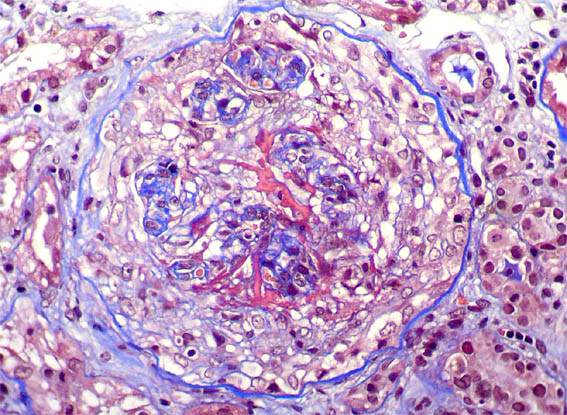

Figura 4. Tricrómico de Masson, X400.